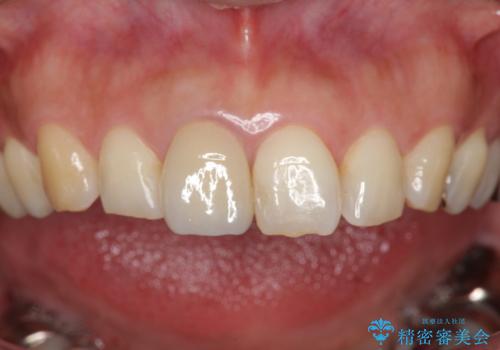

折れてしまった前歯 オールセラミックによる審美改善

- 「野菜をかじった際に前歯がぐらつき、その場で取れてしまった。前歯を入れたい。」と希望され来院されました。

残っている歯質(歯の量)は非常に少ないものの、歯を抜かずに残したい希望が強く、また破折リスクが高いことも

ご理解いただいた上で歯を残しセラミック治療を計画します。